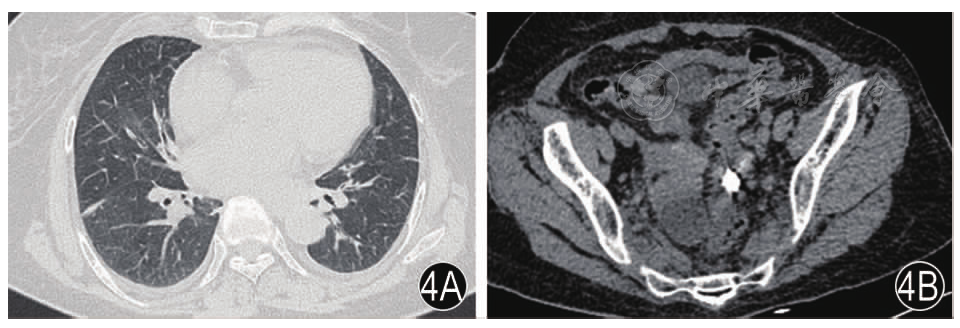

图3 术后第1天复查CT注:3A肺部感染加重;3B盆腔积气积液;3C和谐夹位置

图4 术后第11天复查CT注:4A肺炎吸收;4B穿孔部位形成包裹性积液